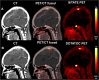

Background: Somatostatin-receptor (SSTR)-targeted PET/CT provides important clinical information in addition to standard imaging in meningioma patients. [18F]SiTATE is a novel, 18F-labeled SSTR-targeting peptide with superior imaging properties according to preliminary data. We provide the first [18F]SiTATE PET/CT data of a large cohort of meningioma patients.

Methods: Patients with known or suspected meningioma undergoing [18F]SiTATE PET/CT were included. Uptake intensity (SUV) of meningiomas, non-meningioma lesions, and healthy organs were assessed using a 50% isocontour volume of interest (VOI) or a spherical VOI, respectively. Also, trans-osseous extension on PET/CT was assessed.

Results: A total of 107 patients with 117 [18F]SiTATE PET/CT scans were included. Overall, 231 meningioma lesions and 61 non-meningioma lesions (e.g., post-therapeutic changes) were analyzed. Physiological uptake was lowest in healthy brain tissue, followed by bone marrow, parotid, and pituitary (SUVmean 0.06 ± 0.04 vs. 1.4 ± 0.9 vs. 1.6 ± 1.0 vs. 9.8 ± 4.6; p < 0.001). Meningiomas showed significantly higher uptake than non-meningioma lesions (SUVmax 11.6 ± 10.6 vs. 4.0 ± 3.3, p < 0.001). Meningiomas showed significantly higher uptake than non-meningioma lesions (SUVmax 11.6±10.6 vs. 4.0±3.3, p<0.001). 93/231 (40.3%) meningiomas showed partial trans-osseous extension and 34/231 (14.7%) predominant intra-osseous extension. 59/231 (25.6%) meningioma lesions found on PET/CT had not been reported on previous standard imaging.

Conclusion: This is the first PET/CT study using an 18F-labeled SSTR-ligand in meningioma patients: [18F]SiTATE provides extraordinary contrast in meningioma compared to healthy tissue and non-meningioma lesions, which leads to a high detection rate of so far unknown meningioma sites and osseous involvement. Having in mind the advantageous logistic features of 18F-labeled compared to 68Ga-labeled compounds (e.g., longer half-life and large-badge production), [18F]SiTATE has the potential to foster a widespread use of SSTR-targeted imaging in neuro-oncology.